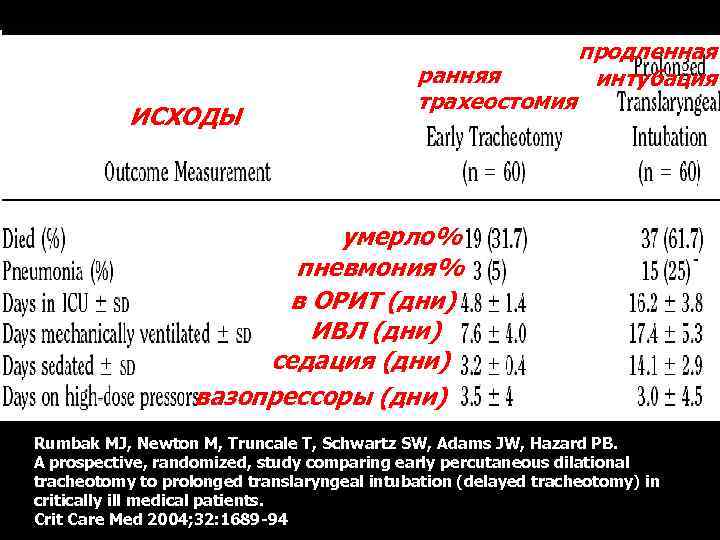

Выгоды ранней (пункционной) трахеостомии

Выгоды ранней (пункционной) трахеостомии

ИСХОДЫ ранняя трахеостомия продленная интубация умерло% пневмония% в ОРИТ (дни) ИВЛ (дни) седация (дни) вазопрессоры (дни) Rumbak MJ, Newton M, Truncale T, Schwartz SW, Adams JW, Hazard PB. A prospective, randomized, study comparing early percutaneous dilational tracheotomy to prolonged translaryngeal intubation (delayed tracheotomy) in critically ill medical patients. Crit Care Med 2004; 32: 1689 -94

ИСХОДЫ ранняя трахеостомия продленная интубация умерло% пневмония% в ОРИТ (дни) ИВЛ (дни) седация (дни) вазопрессоры (дни) Rumbak MJ, Newton M, Truncale T, Schwartz SW, Adams JW, Hazard PB. A prospective, randomized, study comparing early percutaneous dilational tracheotomy to prolonged translaryngeal intubation (delayed tracheotomy) in critically ill medical patients. Crit Care Med 2004; 32: 1689 -94

ИСХОДЫ ранняя трахеостомия умерло% пневмония% в ОРИТ (дни) ИВЛ (дни) седация (дни) вазопрессоры (дни) продленная интубация 5% 25% Rumbak MJ, Newton M, Truncale T, Schwartz SW, Adams JW, Hazard PB. A prospective, randomized, study comparing early percutaneous dilational tracheotomy to prolonged translaryngeal intubation (delayed tracheotomy) in critically ill medical patients. Crit Care Med 2004; 32: 1689 -94

ИСХОДЫ ранняя трахеостомия умерло% пневмония% в ОРИТ (дни) ИВЛ (дни) седация (дни) вазопрессоры (дни) продленная интубация 5% 25% Rumbak MJ, Newton M, Truncale T, Schwartz SW, Adams JW, Hazard PB. A prospective, randomized, study comparing early percutaneous dilational tracheotomy to prolonged translaryngeal intubation (delayed tracheotomy) in critically ill medical patients. Crit Care Med 2004; 32: 1689 -94